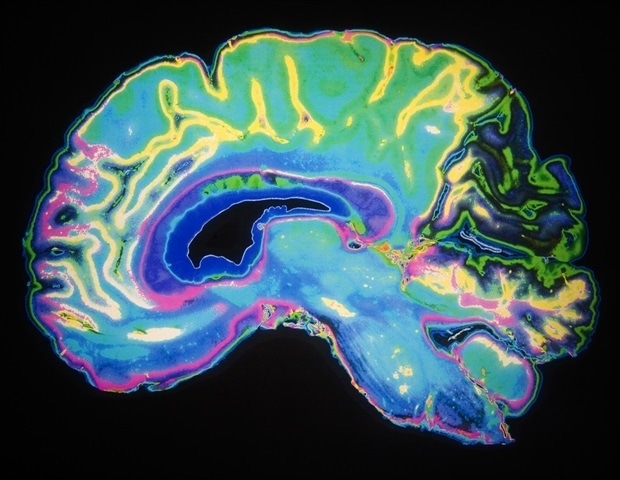

После черепно-мозговой травмы (ЧМТ) некоторые пациенты могут полностью выздороветь, а у других сохраняется тяжелая инвалидность. Точная оценка прогноза затруднена у пациентов, находящихся на аппаратах жизнеобеспечения. Хотя функциональная МРТ в состоянии покоя (rs-fMRI) может оценить неврологическую активность вскоре после травмы головного мозга, неизвестно, предсказывает ли связь между областями мозга на этом раннем этапе долгосрочное восстановление. Исследователи из Mass General Brigham и сотрудники из США и Европы проанализировали данные трех перспективных групп, состоящих из 97 пациентов, которым была проведена rs-fMRI после травмы, и обнаружили, что ранняя связь между тремя парами областей мозга связана с благоприятными функциональными результатами через шесть месяцев. Результаты опубликованы в PNAS.

Исследователи проанализировали сканирование мозга (фМРТ в состоянии покоя) половины участников с ЧМТ, выявив две модели, в которых разные области мозга работали противоположным образом, и третью, в которой области работали вместе. Люди с любым из трех паттернов с большей вероятностью имели лучшие результаты, даже после поправки на такие факторы, как седация и уровень сознания. Исследователи включили свои выводы в модель для прогнозирования результатов после ЧМТ. Они протестировали новый метод на другой половине участников. Эта модель лучше прогнозировала выздоровление, чем более старые модели прогнозирования.

Одна закономерность, которая с уверенностью предсказывала положительные результаты, включала части сети значимости, координационного «концентратора» для многих сетей мозга и сети режима по умолчанию (DMN), которая активна во время отдыха. Вместе эти регионы обеспечивают сознательный доступ к поступающей информации. Другая модель включала области, участвующие в когнитивном контроле и базовой визуальной обработке. Связь между DMN и языковой сетью также помогла предсказать результаты.